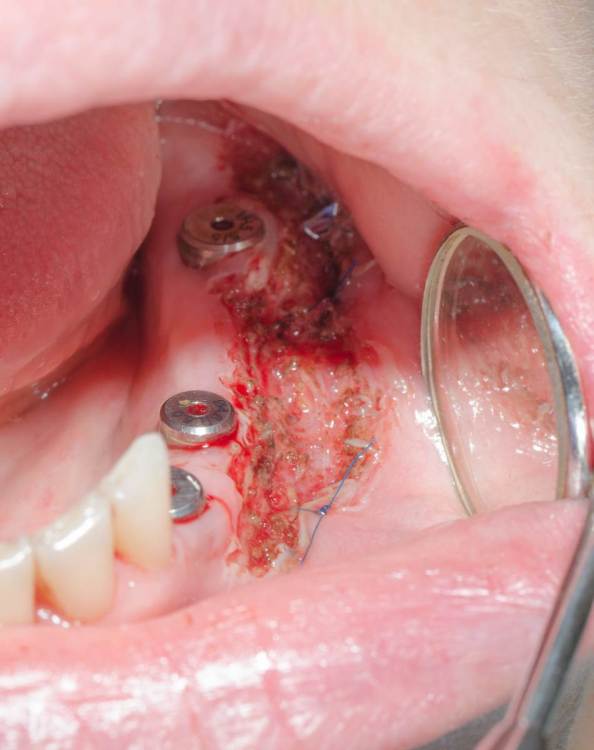

Работе уже 4 года но как то не хотел выкладывать,  так как сам не видел  отдаленный результат. Вот пациентка пришла на осмотр и я снял конструкцию потому что мы оба забыли что она стояла на темп-бонде. Десну отдавливал сразу постоянными.

До

между фотографиями при открытии 6 ки был подсажен ССТ. Объем увеличился, а кератинизации не увидел, решил сделать смещение лоскута лазером.